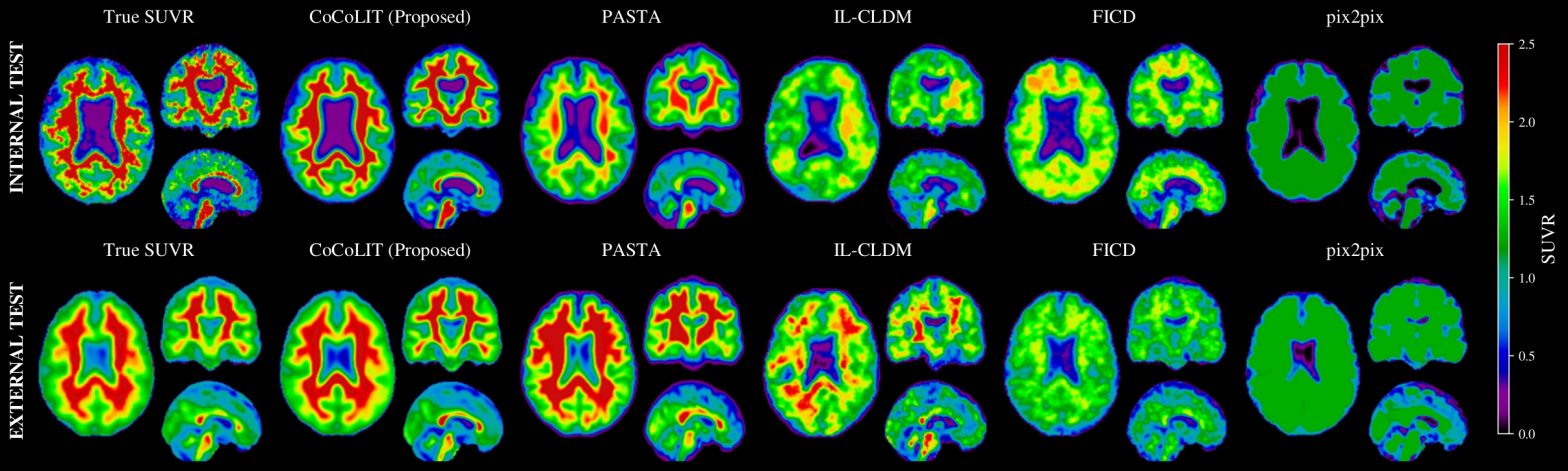

- Test su dataset reali di Alzheimer: CoCoLIT supera tutti i precedenti metodi in accuratezza di image synthesis e classificazione amiloide.

- SIGNIFICATIVO: +10,5% di accuratezza bilanciata su dataset interno, +23,7% su dataset esterno.